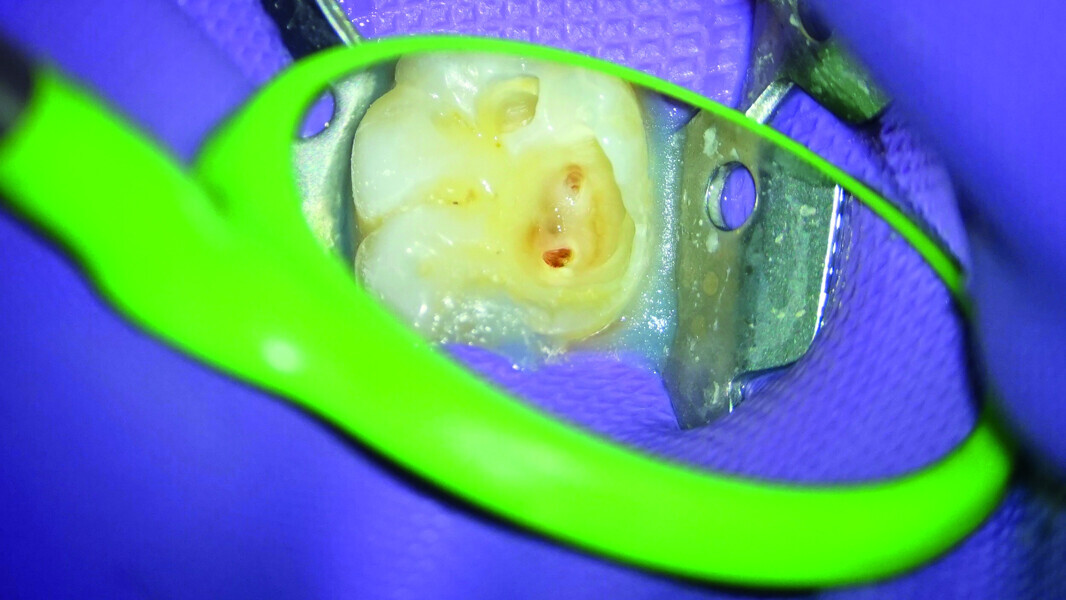

Direct pulp capping as a conservative procedure to maintain pulp vitality